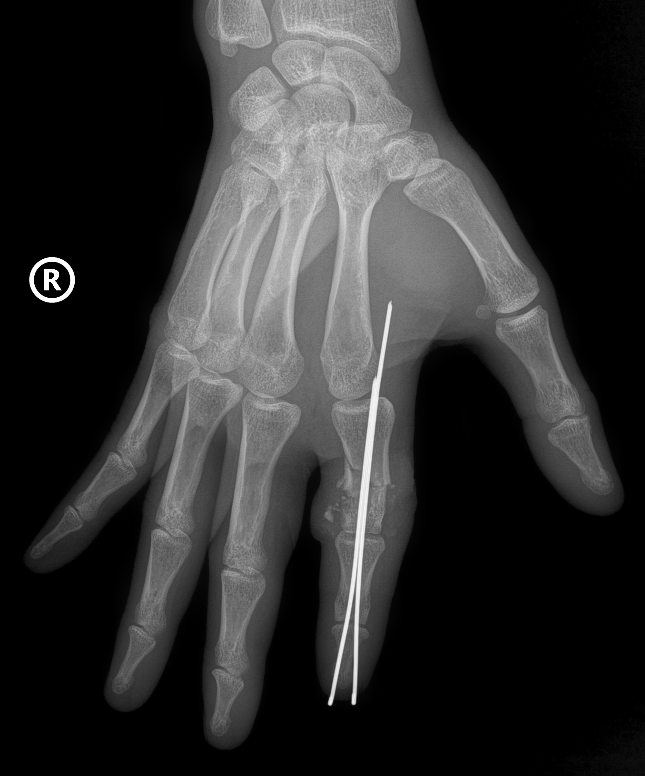

| Hình ảnh phần ngón tay bị đứt rời của bệnh nhân được định vị và cố định bằng kim chuyên dụng - Ảnh: VGP |

Xương ngón được định vị và cố định bằng kim chuyên dụng để tạo trục vững, hệ thống gân và dây chằng được phục hồi. Đặc biệt là thần kinh và các mạch máu nhỏ li ti chỉ khoảng 0,8 - 1mm được phục hồi với độ chính xác cao dưới kính hiển vi phẫu thuật cùng dụng cụ đặc biệt, nhằm đảm bảo phục hồi lưu thông tưới máu cho phần đứt rời.